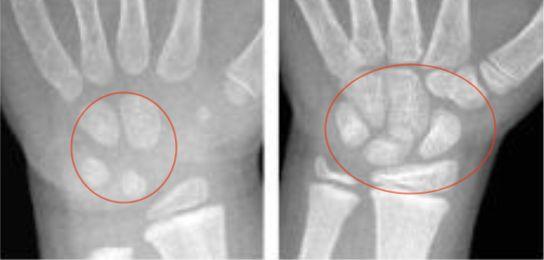

病例讨论第124期丨猜猜这个孩子多少岁看腕骨判断年龄也有不准的时候

了解孩子骨龄情况时,通常要拍摄孩子左手手腕部的x光片,而检查医生

骨龄怎么拍?为什么选择「左手手腕」作为骨龄标志?